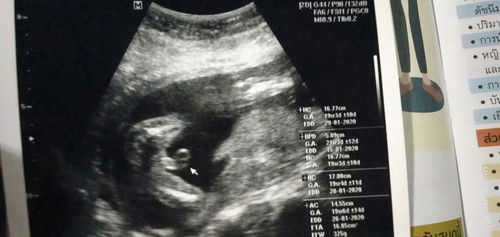

ญ รึ ช คะ

แม่ๆคะผู้หญิงรึผู้ชายคะช่วยดูหน่อยจร้า

เหมือนจะชายนะค่ะ